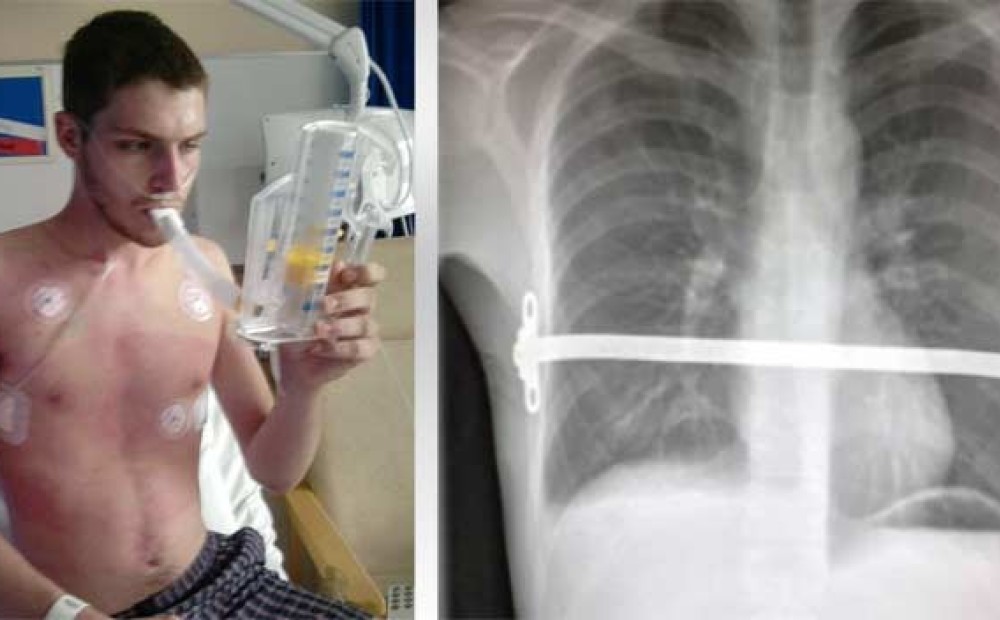

Операция Грудной Клетки Фото